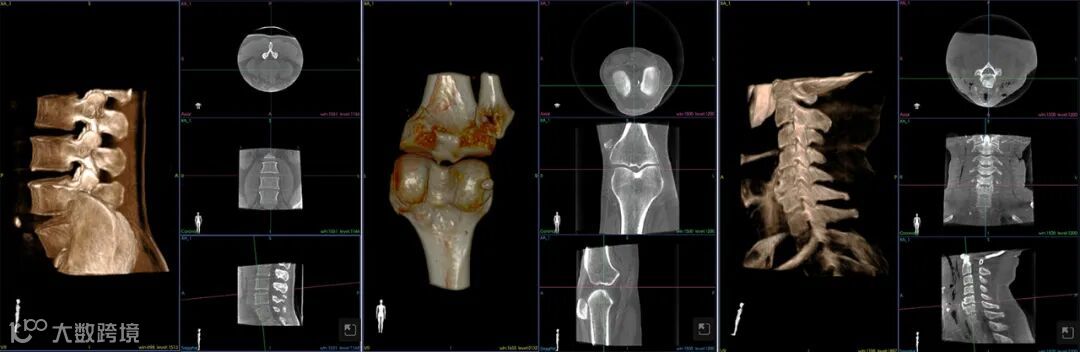

另外,刘新宇教授对歌锐术中CBCT也给予了高度评价。他表示,歌锐CBCT仅用12s~14s即可完成影像扫描及三维重建,节省了时间,图像精度达0.16mm,满足了外科精准手术的需求,此外,偏心投照的设计十分人性化,为通道穿刺等临床工作提供了便利。

专门开发的“牛顿”3D高精度术中CT可获得超高精度影像,是微创手术规划和执行的基础

“牛顿”系统涵盖术中高精度CBCT采集、一键式智能手术规划、精准手术通道一体化成型、力反馈的主从式手术操作以及术后影像评估和分析等全方位的各个环节,做到了全程深度参与,临床价值、实用性、扩展性大大提高,实现了该领域“零的突破”。